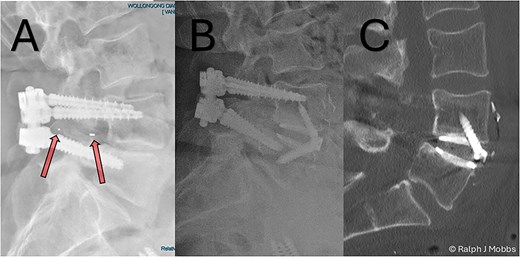

This case report illustrates a novel two-stage revision strategy for symptomatic L4/5 pseudarthrosis (Fig. 1A), integrating anterior lumbar interbody fusion (ALIF) with posterior endoscopic cage retrieval and decompression. The initial ALIF procedure (Fig. 1B) enabled restoration of segmental lordosis, disc height, and immediate biomechanical stability, while also facilitating distraction of scarred posterior elements. This was followed by a targeted, minimally invasive endoscopic procedure to remove the failed TLIF cage and decompress neural elements (Video 1), thereby avoiding the morbidity of an open posterior revision.

(A) Initial presentation with TLIF cage migration posteriorly into the spinal canal and paraspinal muscles. (B) Stage 1 and 2 completion, including revision fusion using an ALIF cage (Redmond Ti/PEEK, A-spine, Taiwan) and TLIF cage removal. (C) CT scan post TLIF removal and disc height restoration with ALIF cage.

A 64-year-old female with a history of a TLIF at L4/5, performed 18 months prior to presentation to the current surgeon, presented with persistent low back pain and radiculopathy. Imaging demonstrated non-union at the TLIF site with ongoing foraminal stenosis and segmental instability (Fig. 1A). Multidisciplinary review determined that a revision fusion was the initial focus as mechanical back pain related to non-union was the primary complaint. Following the planned stage 1 intervention, removal of the migrated TLIF cage was determined necessary as the device was serving no purpose and likely causing further symptoms. Therefore, a two-stage revision strategy was planned.

Stage one: anterior lumbar interbody fusion

Following standard preoperative preparation, the patient underwent ALIF at L4/5 (Fig. 6). A standard retroperitoneal approach and anterior discectomy were performed [4], with the disc space prepared. Note was made that no graft was within the interbody space, nor any evidence of arthrodesis. A Redmond Ti/PEEK ALIF cage (A-Spine, Taiwan) 14 mm, 12° lordotic cage was inserted with three integral 30 mm screws for segmental fixation (Fig. 1B and C). The ALIF device and interbody space were packed with allograft and autograft material. The construct was confirmed with intraoperative X-ray imaging, and postop CT scan the following day (Fig. 2). Estimated blood loss was minimal (~15 cc), with no intraoperative complications.